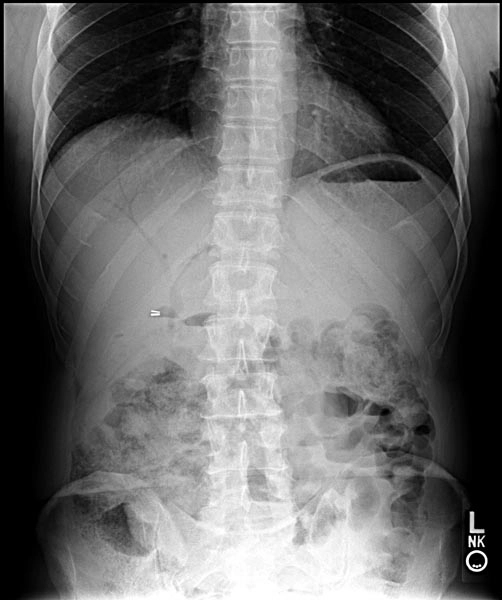

• Xoắn túi mật (Gallbladder volvulus)

• Khí trong đường mật (Pneumobilia)